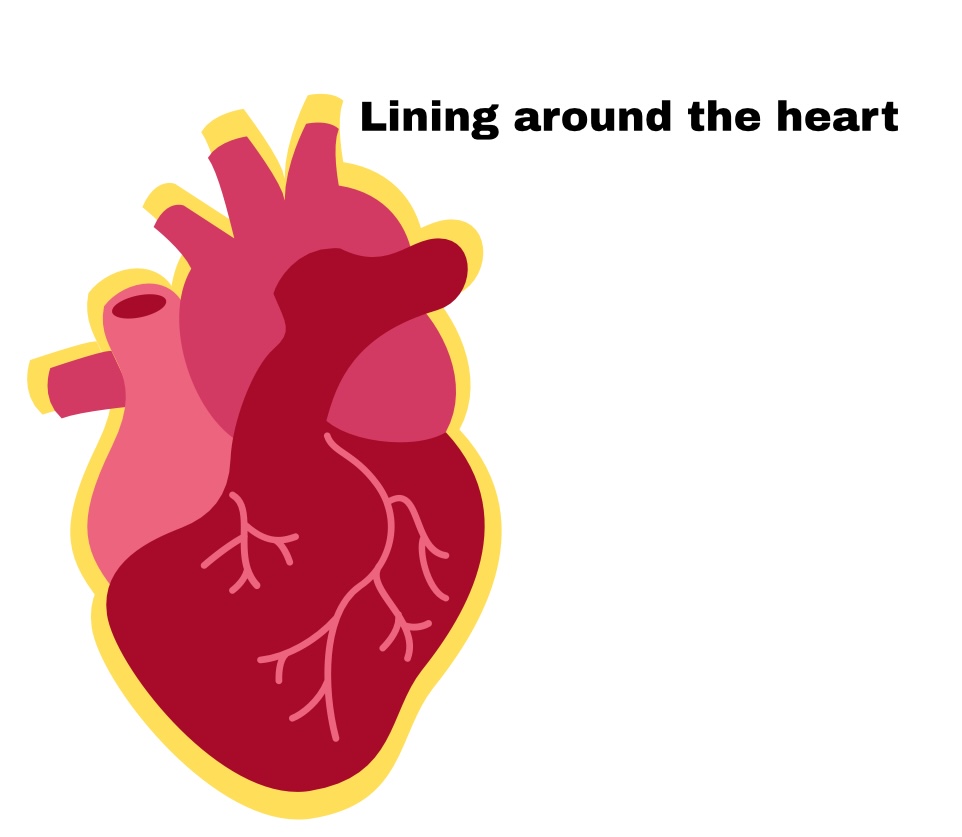

The heart=

Pericardium

Pericardium

Sac around heart

Partial Pericardium

Outer layer

Visceral Pericardium

Deep layer (surface of organ)